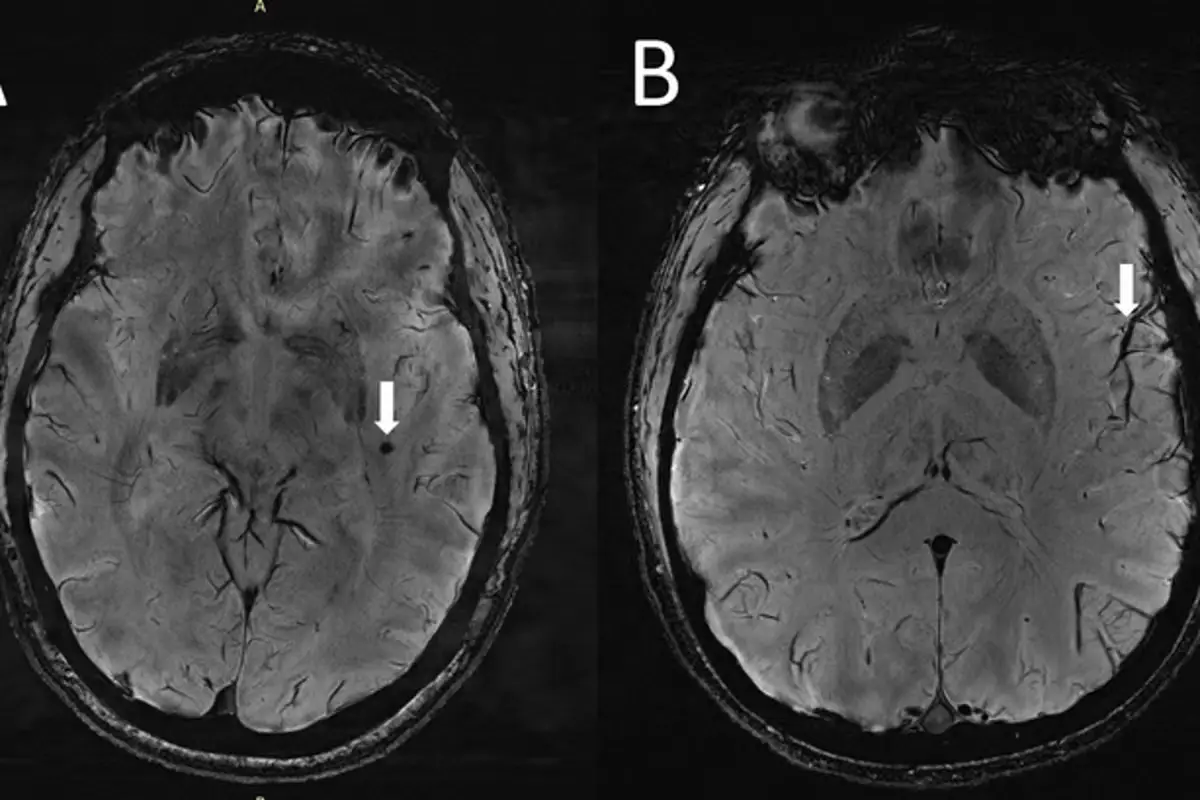

Getting advanced MRI scans of the brains to identify tiny changes between the brains, the researchers found 'significant changes' in the brains of migraine sufferers.

He said: "Because 7T MRI is able to create images of the brain with much higher resolution and better quality than other MRI types, it can be used to demonstrate much smaller changes that happen in brain tissue after a migraine.

"In people with chronic migraine and episodic migraine without aura, there are significant changes in the perivascular spaces of a brain region called the centrum semiovale."

"These changes have never been reported before."